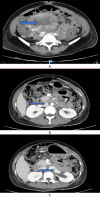

This clinical report discusses the interplay of various pathologies that may present similar clinical manifestations, with uncertainty about the distinct impact of each one of them. The patient is a 43-year-old young Asian female with no known medical conditions. She was 33 weeks pregnant when she was admitted for an urgent c-section because of preeclampsia with HELLP syndrome. While hospitalized, she complained about the visual field's loss. A comprehensive ophthalmological examination revealed a severe concentric visual field defect along with well-reduced visual acuity and impaired color vision. Her OCT revealed a bilateral serous macular detachment related to pre-eclampsia. A brain MRI revealed a microstroke at the temporo-parieto-occipital junction (TPO), although it did not fully account for the severity of the visual field deficit. Despite the macular pathology being resolved, the visual field remained deeply impacted. A thorough and complete investigation yielded negative results, leaving the cause of the patient's deficit unknown. The patient likely had a normal pressure glaucoma. Additionally, multifactorial bilateral microvascular ischemic neuropathy (caused especially by high myopia) has significantly affected her visual field. Furthermore, it is also probable that the patient had genetic neuropathy. Initial genetic testing was negative; however, due to the high suspicion of a genetic component, a retest was conducted, and the results were not conclusive. This case represents a highly unusual case of a profoundly affected visual field with no apparent identified cause. This is a notable example of the potential interaction of various local and systemic pathologies that can manifest with similar clinical presentations.